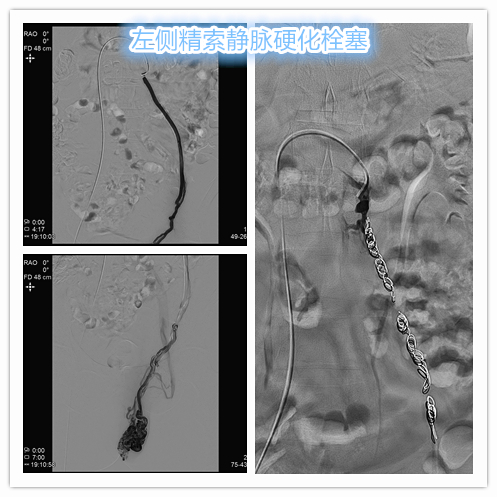

介入硬化栓塞治疗采用经皮穿刺插管方式,经股静脉、颈静脉或肱静脉途径,选择性插管至精索静脉,使用弹簧圈+泡沫硬化剂对靶血管进行硬化栓塞治疗,从而达到闭塞精索静脉主干目的,阻断血流返流。

- 行左侧精索静脉造影显示左侧精索静脉明显扩张、迂曲,血流逆流。予以超选插管至左侧精索静脉中下段行弹簧圈栓塞+泡沫硬化栓塞治疗。复查造影显示左侧精索静脉主干闭塞。

左侧精索静脉介入硬化栓塞